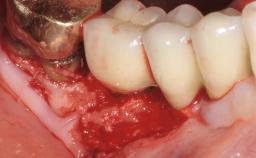

Treatment of Peri-Implant Mucositis at a Zirconia Implant